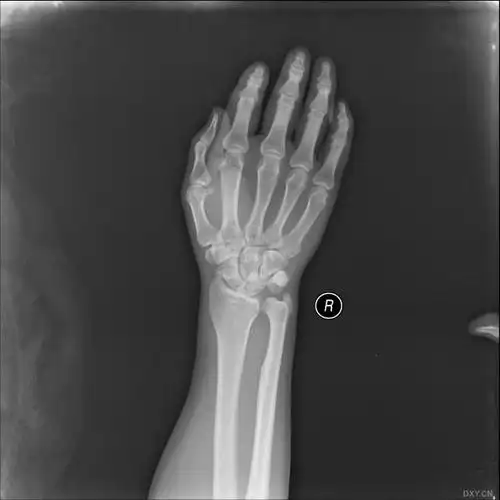

【读片】腕关节脱位 [病例帖]